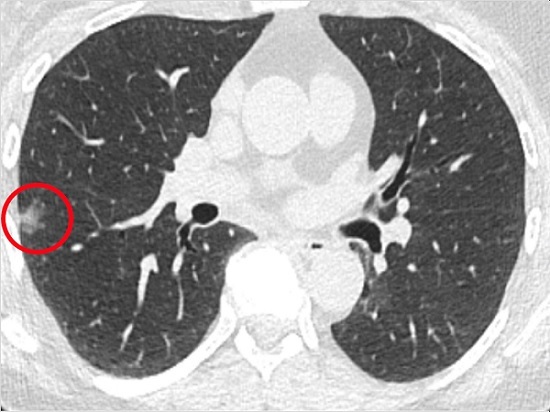

5月23日据photonics media报道,美国宾夕法尼亚大学艾布拉姆森癌症中心的研究人员开发了一种在活检过程中实时检测肺癌细胞的方法。该方法可以帮助医生在癌症早期就能检测到可能太小而无法使用现有技术检测到的癌细胞。

可疑组织的活检并不总是有效的。很多时候,相关结节可能太小而无法看到,这导致许多患者和医生不确定患者体内是否存有癌细胞,并且需要进行额外的活检和放射学监测,直到结节大到可以通过组织病理学评估看到切除和评估。此过程可能需要几天时间才能完成。此外,当前的医疗技术在活检期间不提供实时诊断信息。

通过NIR-nCLE发现这些微小结节的方法,可以为医生提供更高的识别精度,并在随后去除癌细胞。研究人员希望这种方法可以帮助早期诊断其他类型的癌症。美国食品和药物管理局最近批准Cytalux用于成年卵巢癌患者手术中的辅助治疗,以识别癌性病变。